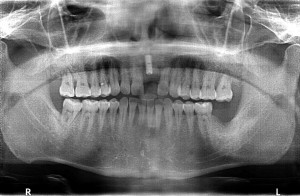

以前、当院で左上7番部にインプラントを埋入させて頂いた既往のある方でした。

左上6番がかなり動揺していたので抜歯をし、

4ヵ月経過したのでCT画像を拝見させていただきました。